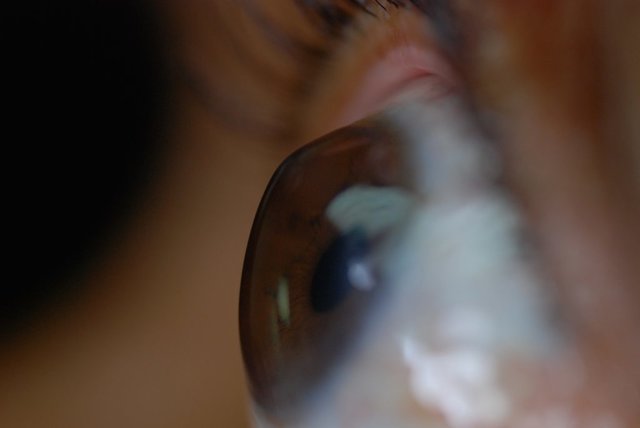

یک جراح و متخصص چشم گفت: با تشخیص به‌موقع، کنترل و درمان قوز قرنیه می‌توان از پیشروی و پیوند قرنیه پیشگیری کرد.

نسیم خبر- دکتر الهام سلطانی با اشاره به اینکه قوز قرنیه چشم یا کراتوکونوس بیماری ارثی غیرالتهابی است، اظهار کرد: غالبا افراد مبتلا به این مشکل، زمینه خانوادگی در این خصوص دارند و معمولا این بیماری با عیوب انکساری به سرعت پیش‌رونده خود را نشان می‌دهد.

وی در ادامه اظهارکرد: فرد مبتلا به قوز قرنیه معمولا با این علائم به ما مراجعه می‌کند که نمره عینکم تند تند تغییر کرده و عینک را زود به زود عوض می‌کنم و این بدان معناست که عینک نتوانسته به‌صورت قابل قبول مشکل بینایی فرد را اصلاح کند.‌

این عضو هیات علمی دانشگاه علوم پزشکی همدان با بیان اینکه تشخیص قطعی با عکسبرداری‌هایی از سطح قرنیه ممکن است، ادامه داد: معمولاً بیماران در سنین ۲۰ تا۳۰ سال به این مشکل مبتلا می‌شوند و شیوع آن در سایر گروه‌های سنی کمتر است.

وی اضافه کرد: درمان‌ها در این بیماران بر حسب شدت و سن بیمار متفاوت است اما معمولا در انواع خفیف بیماری، عینک یا لنز نرم ممکن است کمک‌کننده باشد ولی با پیشرفت بیماری و نازکتر شدن و تغییر شکل بیشتر قرنیه این درمان‌ها دیگر چندان کارساز نخواهد بود.

سلطانی در ادامه اظهارکرد: درمان بعدی بیماری استفاده از لنزهای سخت دارای قابلیت نفوذ گاز است، این لنزها قابلیت بیشتری برای اصلاح آستیگاتیسم نامنظم ناشی از کراتوکونوس (قوز قرنیه) دارند اما در حال حاضر در بیمارانی که قادر به تحمل لنزهای سخت نیستند از روش‌های جدیدتری مانند قرار دادن رینگ‌های داخل قرنیه مثل Intacs و Ferrara و رینگ کامل Myoring استفاده می‌شود.

وی با اشاره به اینکه یکی از روش‌های درمان قوز قرنیه، روش جراحی کراس‌لینکینگ است که باعث استحکام قرنیه و پیشگیری از پیشرفت بیماری است، گفت: در این روش بینایی فرد با و بدون عینک بهبود یافته و میزان آستیگماتیسم، کاهش قابل ملاحظه‌ای خواهد داشت و این روش باعث می‌شود به پیوند قرنیه نیاز نباشد.